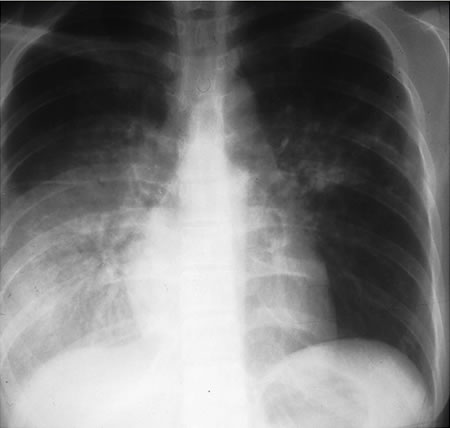

Pulmonary tuberculosis

Opacities in right lower lobe in a patient with pulmonary TB and diabetes

From the personal collection of David Horne and Masahiro Narita; used with permission